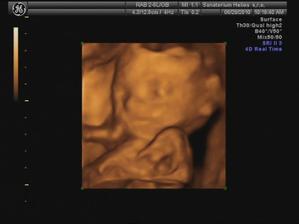

29.6. jdeme na 3D ultrazvuk 🙂 těšíme se... - bylo to úžasný 🙂 cena sice vyšší, ale jedna barevná fotka tištěná, 3 fotky na mail a téměř půlhodinové video, ze kterého jsme si doma udělali ještě asi 120 fotek 🙂